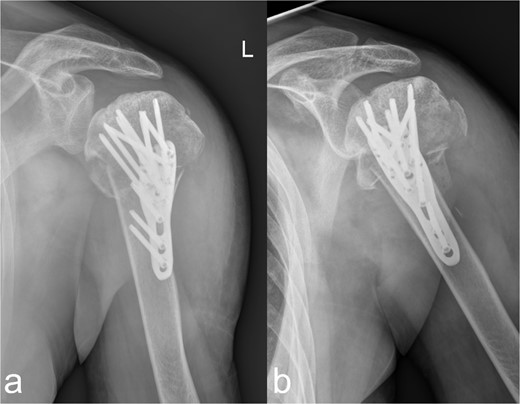

Using a 3-hole LCP plate (PHILOS-Synthes®) for the humerus (Fig. 4a and b) and a locking T-plate with two additional screws (Synthes®) for the caput and collum radii (Fig. 5a and b), adequate reduction and mostly axial alignment of the fractures were achieved.

Treatment patterns of the subcapital humerus fracture (11C3.1). (a, b) The radiographs in two planes show extensive coverage of the fracture fragments with adequate stabilization of the multiple fragment fracture of the caput humeri, which was treated osteosynthetically using a PHILOS® plate and multiple screws.